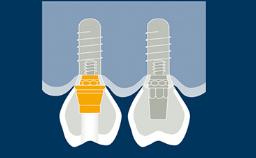

With the introduction of intraoral scanners and the widely used application of implant-supported prostheses produced using CAD/CAM - or Computer-Aided Design/Computer-Aided Manufacturing - it is possible to digitize implant positions directly in the patient's mouth.

Making intraoral scans of implants, rather than digitizing plaster casts based on conventional impressions, saves a number of steps in the restorative process. With fewer steps, there is potentially also less risk of errors and discrepancies. This module will focus on the applications of intraoral scanning of dental implants.